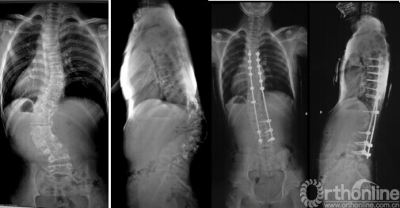

14岁男性患儿,先天性脊柱侧凸骺阻滞术后11年、重度僵硬性侧后凸畸形,行顶椎区域多段脊椎截骨术,术前术后X线片及外观对比